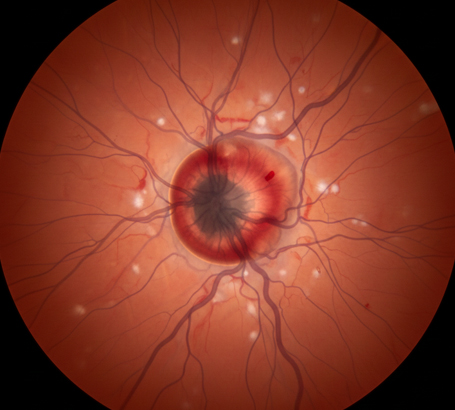

Optic Neuritis Inflammation of the optic nerve causing pain (especially with eye movement) and sudden vision loss.

Optic Neuropathy Damage to the optic nerve due to conditions such as diabetes, glaucoma, reduced blood flow (ischemia), or nutritional deficiencies.

Papilledema Swelling of the optic nerve head due to increased pressure inside the skull.

Papilledema: Swelling of the optic disc due to increased brain pressure.

Ischemic Optic Neuropathy: Loss of blood flow to the optic nerve.

What is Optic Nerve Atrophy?

Optic nerve atrophy is the end stage of various diseases that damage the optic nerve. It results in a pale optic disc and permanent vision loss. Early diagnosis is critical to stop the progression of the underlying cause before atrophy occurs.